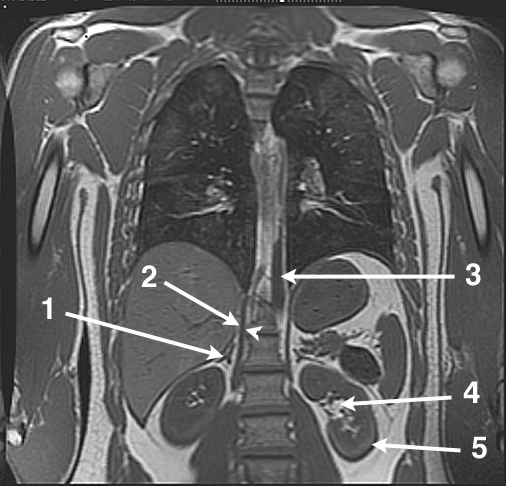

Identifications